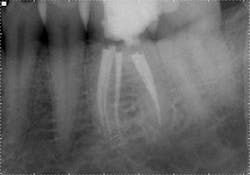

The WaveOne shape in the four main canals allowed for obturation with a warm vertical technique, because the heat source could be delivered to within a few millimeters of the apex. However, the constricted shape of the mid-mesial was not amenable to this technique and a GuttaCore carrier was placed to take advantage of the hydraulics and create a dense, three-dimensional seal.

This case illustrates an alternative method of hybridizing the shaping technique based on the natural canal anatomy. In spite of highly variable anatomy in the mesial root, different instrumentation and obturation techniques yielded a final outcome that cannot be distinguished radiographically.